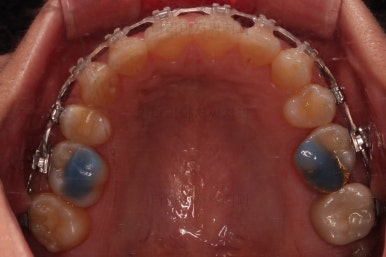

4. 마무리

할 수 있는 부분과 수용한 부분을 구분해서 환자분과 적절히 치료계획을 타협하고요. 치료를 마무리합니다.

가지런한 느낌 좋고요.

교합도 잘 맞고 이 뽑은 자리도 틈이 없으며 사랑니 당겨온 자리도 틈새 없이 잘 마무리가 되었네요.

전반적으로 깔끔하게 임플란트 없이 결손치아 부분을 잘 마무리 했습니다.